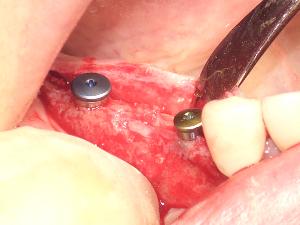

治癒期間の目安上顎前歯/上顎奥歯:3~6ヶ月 下顎前歯/下顎奥歯:3ヶ月